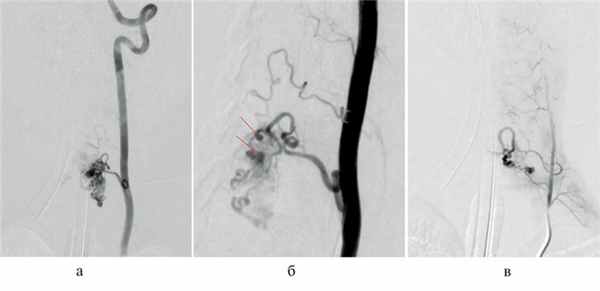

В стационаре выполнили МРТ шейного отдела позвоночника (рис. 1) и селективную спинальную ангиографию. По данным ангиографии, на уровне СVI—СVII позвонков выявлена спАВМ гломусного типа с наличием интранидальных аневризм и кровоснабжением из корешковых артерий, отходящих от левой позвоночной артерии и восходящей артерии шеи левого щитошейного ствола (рис. 2, а—в). Венозный дренаж осуществлялся в спинальные вены и венозное сплетение спинного мозга (рис. 3).

Рис. 2. Селективная спинальная ангиография.

а, б — селективная ангиография левой позвоночной артерии; определяется интрамедуллярная артериовенозная мальформация, кровоснабжаемая из корешковой артерии, с наличием интранидальных аневризм (стрелки); в — селективная ангиография щитошейного ствола слева, определяется дополнительное кровоснабжение артериовенозной мальформации из восходящей артерии шеи.